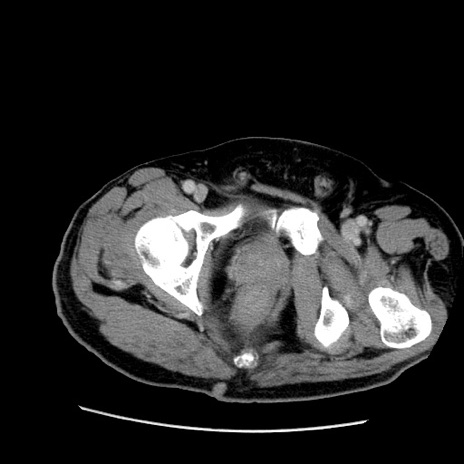

症例22(横断像)

【症例】50歳代男性

【主訴】腹痛

【現病歴】AVMからの被殻出血のため回復期リハ病棟入院中。 本日午後3時頃急に下腹部痛が出現した。

【既往歴】AVM、被殻出血、虫垂炎、高血圧

【身体所見】意識晴明、左半身不全麻痺、会話の理解は良好、36.5°C、腹部:膨隆、全体に板状硬、下腹部正中に圧痛点あり、反跳痛-、筋性防御不明、右下腹部にope scar

【データ】WBC 9400、CRP 0.06